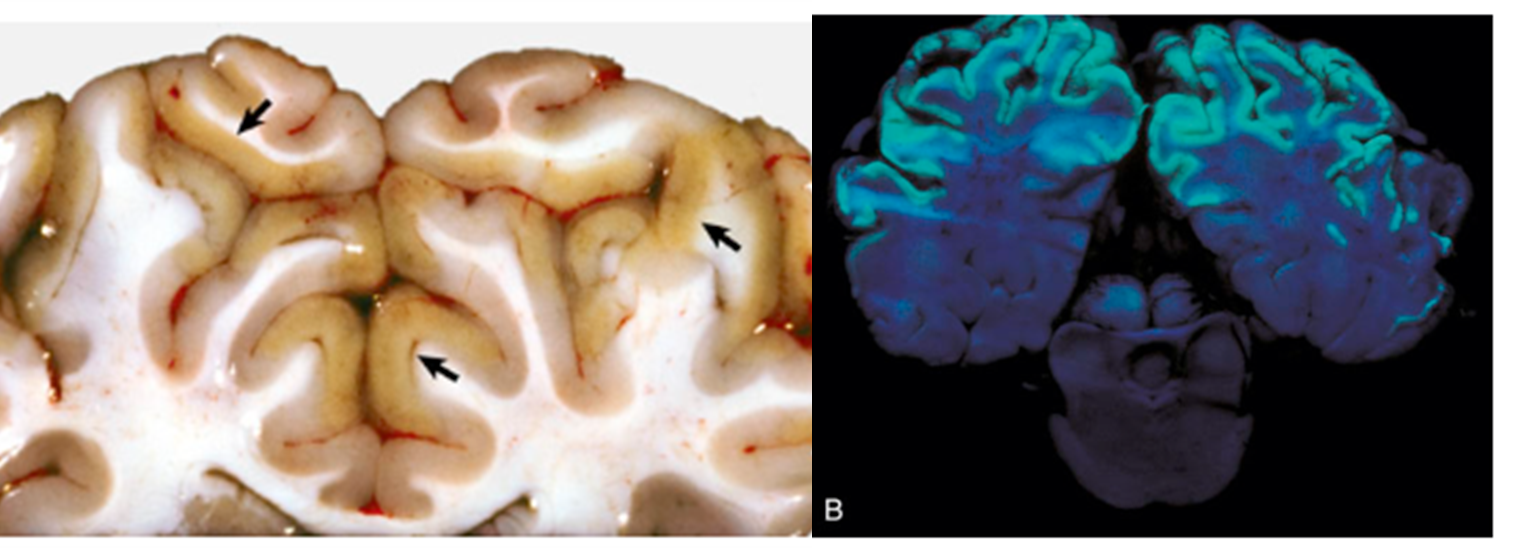

New cards

What pathology is shown in this image?

bilateral cerebrocortical lesions in a small ruminant indicating copper deficiency

Polioencephalomalacia (image)